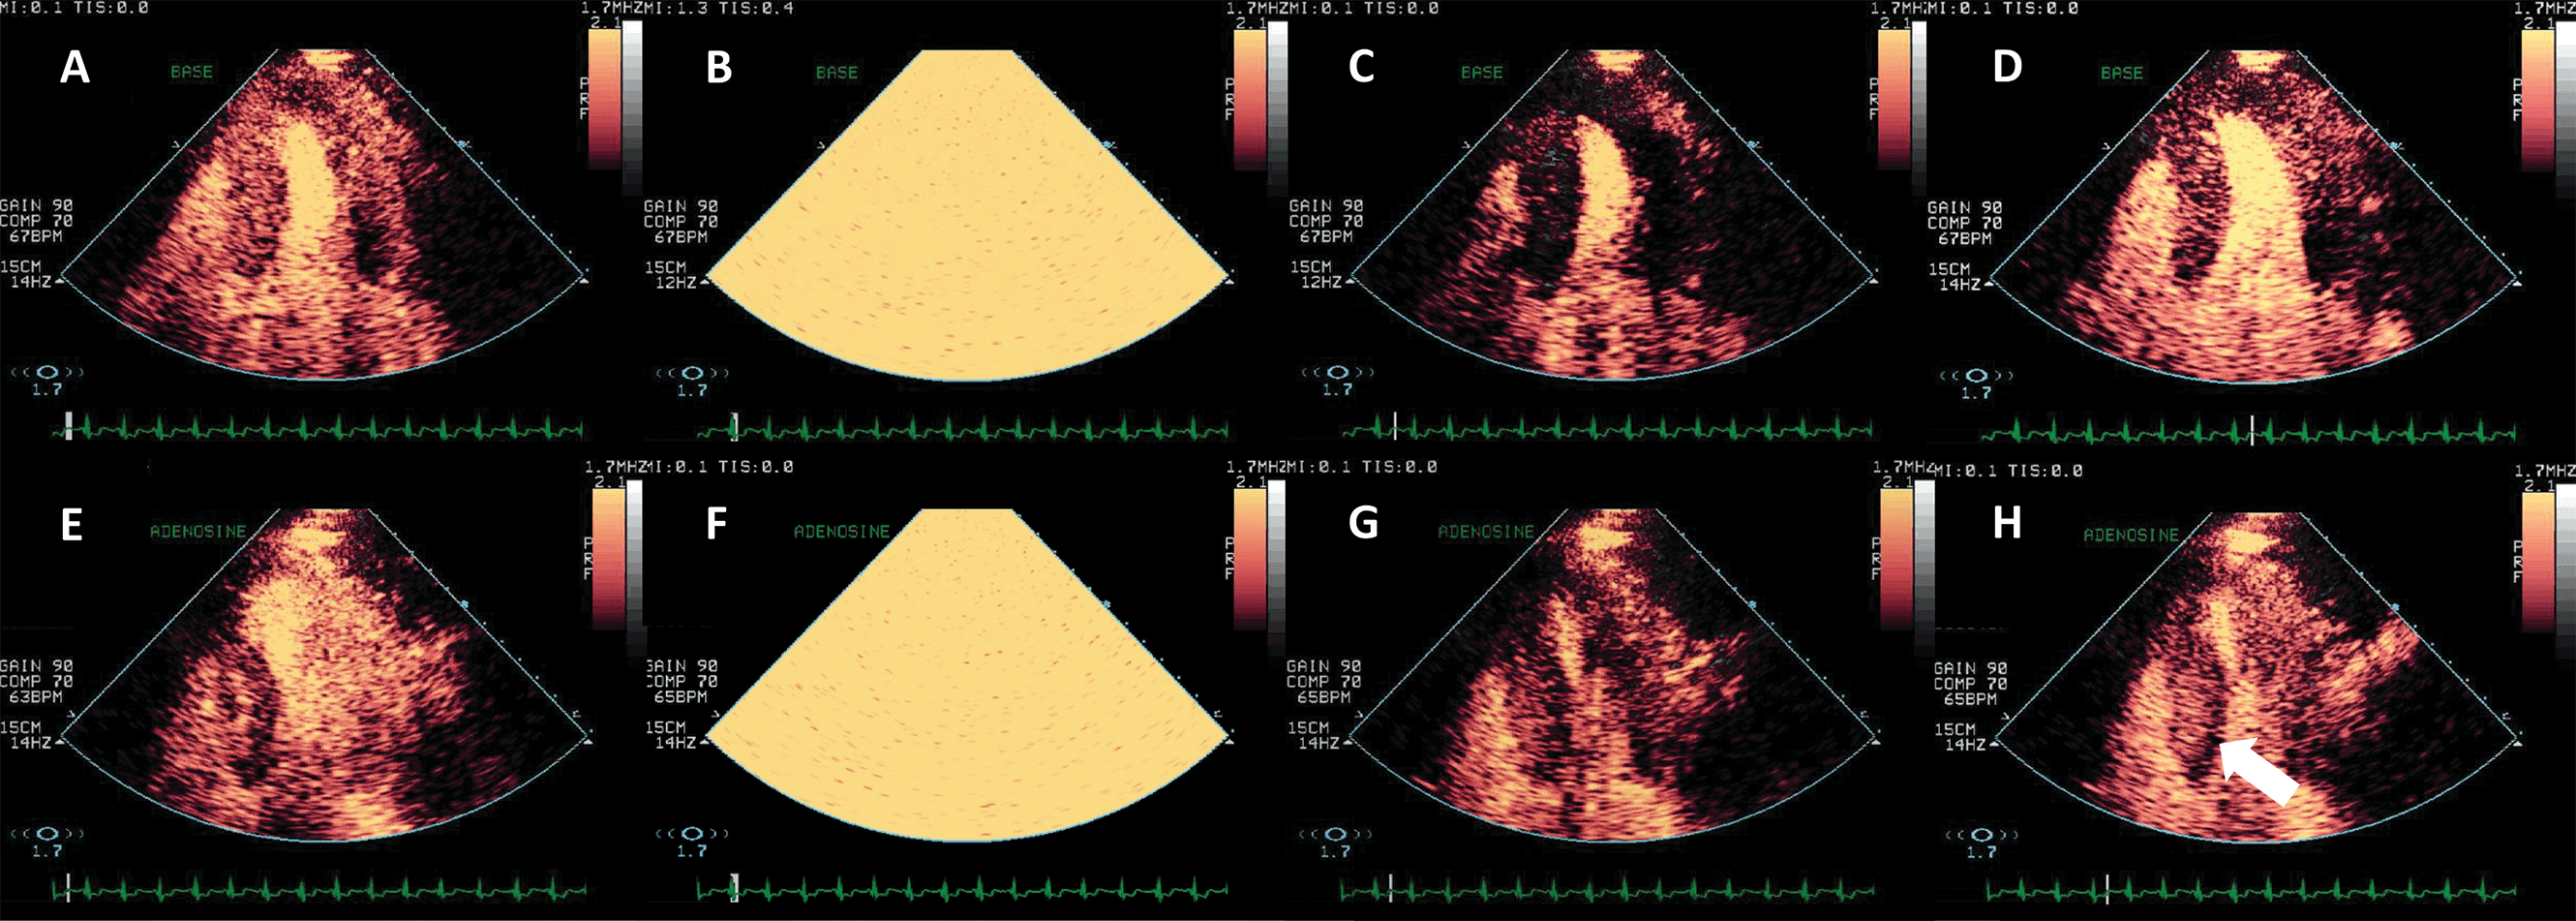

Assessing myocardial perfusion has incremental benefit over wall motion analysis in detecting coronary artery disease (CAD) [55]. The myocardial contrast signal obtained in a steady state (continuous infusion) can be normalized to the LV cavity signal and this represents the myocardial capillary volume [54]. By delivering a series of high-power (high mechanical index) ultrasound frames to the region of interest, cavitation and destruction of the UEA bubbles is initiated; the analysis of the progressive recovery of the contrast signal in the myocardium provides information on the myocardial capillary flow [54, 55, 56] (Fig. 9, Video 8).

Fig. 9.Vasodilator stress echocardiography with Adenosine, using a low-MI setting and flash-replenishment technique. (A–D) Baseline end-systolic frames before flash (A), flash (B), immediately post flash (C, myocardium is dark because of the destruction of contrast), and post-replenishment frame (D) when perfusion is again homogeneous. (E–H) After adenosine infusion, the same order of frames. (H) Post replenishment end-systolic frame demonstrating a subendocardial perfusion defect in the inferosetptal segements (arrow). Of note, during stress myocardial replenishment occurs faster than at rest because of the pharmacological vasodilation. The patient underwent coronary angiography and stent placing in the right coronary artery. Source: personal collection.